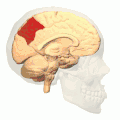

![]() Medial surface of left cerebral hemisphere. (Precuneus visible at top left.) (Anterior to the right.) | |

Medial surface of left cerebral hemisphere. (Precuneus visible at top left.) -